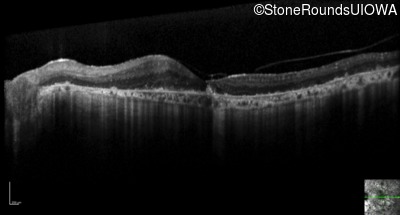

Optical Coherence Tomography - Left - 20/63 +2

Exemplar / OCT Stack

OCT Stack